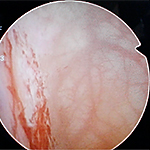

- 膀胱水圧拡張術は保険で認可された唯一の治療法です。

- 膀胱水圧拡張術は診断、治療として有用ですが、治療効果は約6ヶ月と言われています。